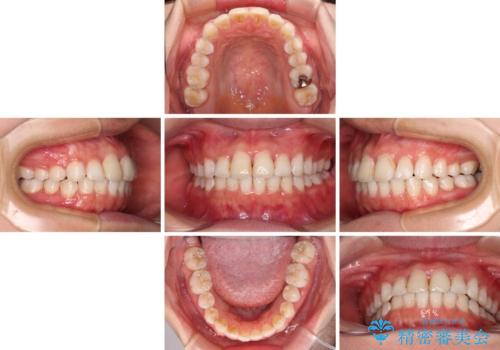

前歯の捻れを改善 インビザラインによる矯正治療

- 前歯の翼状捻転を気にして来院された患者様です。

全体的に叢生は軽度であったため、インビザラインにて矯正治療を行うこととしました。

前歯の幅の大きさも気になっていたため、IPRにより叢生を解消するとともに、歯の大きさも改善しました。